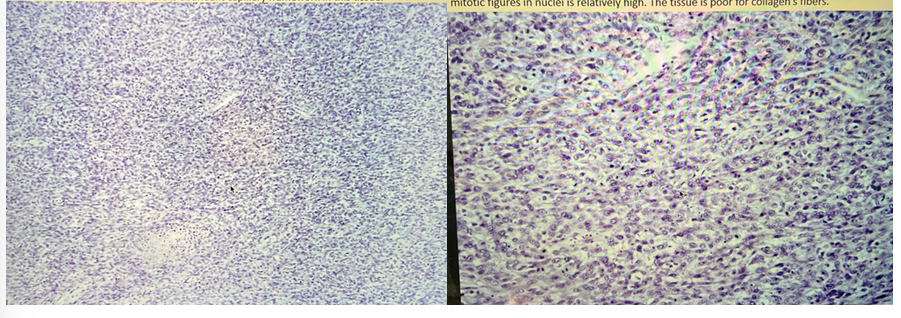

fibrosarcomna uteri

this is?